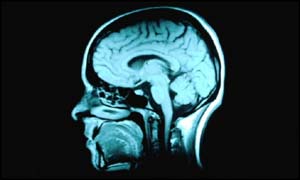

| Tuesday, 19 November, 2002, 10:55 GMT Brain damage link to sleep disorder  The scientists scanned the brains of patients Stuttering and a serious sleep disorder may both be linked to brain damage, scientists believe. Researchers in the United States have found that patients with sleep apnoea have fewer brain cells in key areas. They are also more likely to have had a speech impediment as a child.

Around 4% of men suffer from sleep apnoea. Sufferers snore very loudly and actually stop breathing several times a night. Traditionally, doctors believed that the condition was caused by enlarged tonsils blocking a narrowed airway. Brain scans But a study by Dr Ronald Harper and colleagues at the University of California Los Angeles suggests that other factors may be to blame. They carried out brain scans on 21 men with sleep apnoea and 21 men without the condition. The scans revealed that men with sleep apnoea had significantly fewer brain cells in areas of the brain that control speech, movement and emotion. The researchers also found that 38% of patients with sleep apnoea had of history of stuttering earlier in their life. This compares to just 7% of the general population. The scientists said this indicated that the origins of the sleep disorder could lie in childhood. Dr Harper said: "Because the sleep apnoea patients possessed speech impairment from childhood and their brain's speech centre revealed significant grey matter loss, this brain damage likely originated early in life." They suggested speech impediments could indicate people at risk of the disorder. "Speech impediments may prove an important diagnostic clue for assessing and treating sleep apnoea," said Dr Paul Macey, one of those involved in the study. "In the future, doctors may monitor certain brain structures and examine children for speech or movement problems that may predict a higher sleep apnoea risk." Further research Professor John Stradling, who works at the Oxford Radcliffe Trust, said further research is needed before a definitive link between stuttering and sleep apnoea could be proved. "This is a hypothesis. There is no obvious reason why there should be a link. We would need a lot more research." Speaking to BBC News Online, Professor Stradling said the suggestion that patients with sleep apnoea suffered brain damage backed up previous findings. "This would suggest that sleep apnoea can cause permanent brain damage. It backs up a recent UK study which found early evidence of damage to the brain. "It suggests that sleep apnoea may cause long term problems of cognition." The study is published in the Journal of Respiratory and Critical Care Medicine. | See also: 09 Sep 98 | Health 16 Apr 02 | Health 01 Aug 02 | Health Internet links: The BBC is not responsible for the content of external internet sites Top Health stories now: Links to more Health stories are at the foot of the page. | |||||||||||||||||||||||||||||||||||||||||||||||||||||||||||||||||||||||||||||||||||||||||||||||||||||||||||||||||||||||||||||||||||||||||||